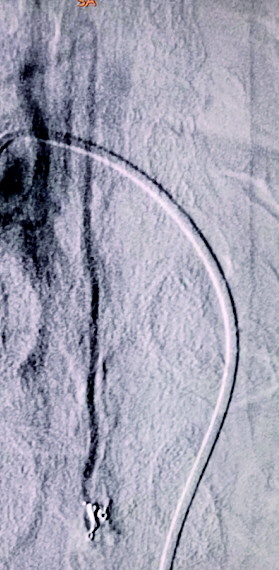

图A为术前造影的正位图像,主供血为脊髓前动脉,引流静脉的起始部形成一个静脉球,远端呈迂曲状;图B为微导管到位后的超选造影,脊髓前动脉不显影(已越过);图C为栓塞结束后的造影,主供血的血流明显瘀滞,瘘口闭塞,下方的脊髓前动脉仍显影。